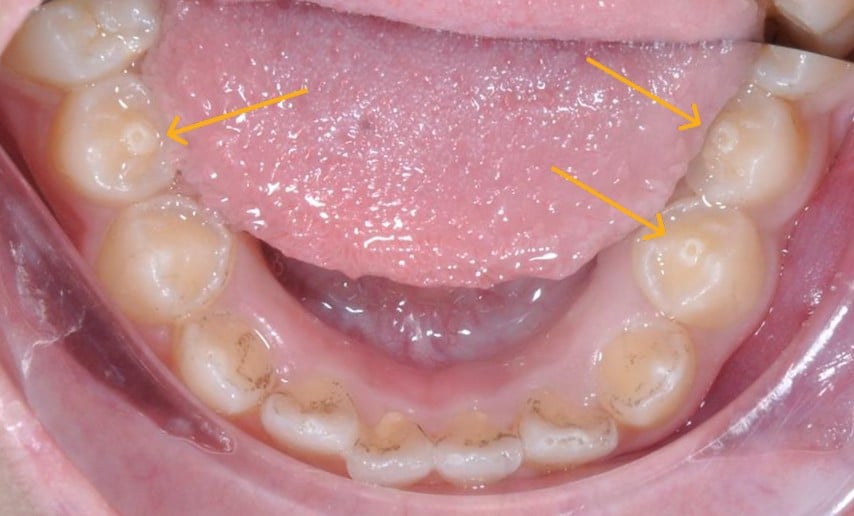

● Másodlagos rügyek a kisőrlőkön: ez egy nagyon gyakori típus, számos betegséget okoz, különösen az alsó kisőrlőkön, gyakran ázsiaiaknál fordul elő. A rügyek a rágófelületen nőnek, élesebb alakúak a normálisnál, könnyen nehezítik a rágást, és harapóerő hatására eltörhetnek.

A legtöbb esetben a plusz rügyek önmagukban jelennek meg, de olyan esetek is előfordulnak, hogy több fogon is vannak plusz rügyek, vagy szimmetrikusan jelennek meg mindkét oldalon. Bár látszólag semmit sem befolyásolnak, rendellenes szerkezetük miatt ezek a fogak hajlamosak a kopásra vagy törésre, különösen erős rágóerő hatására. Ilyen esetekben, ha a rügyek pulpát tartalmaznak, a fog súlyosan fájdalmas lehet, és akut pulpitis alakulhat ki, ami azonnali kezelést igényel a fog megőrzése érdekében.